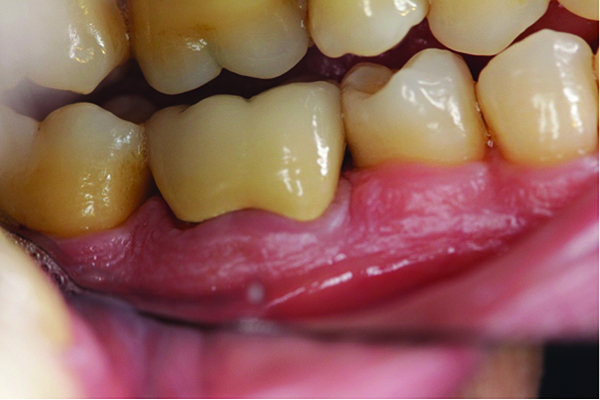

Fig 2. Bucccal caries retain biofilm and food debris, which cause halitosis.

Figure 2

Clinical and radiographic examinations are essential to diagnose dental pathologies. Carious lesions, defective restorations, or fractured cusps, restorations or teeth (Figure 2 and Figure 3) can be sources of malodor both due to food impaction and foul odor associated with necrotic pulp tissue in cases of severe decay.10 Proper excavation, restorations, and regular follow-up are essential for the successful treatment of these patients. Areas of food impaction should be evaluated for restorations to close the embrasure space. Proper instruction of home care via dental floss and/or interproximal brushes is also required. An individual prone to caries as the source of malodor may also benefit from the adjunctive use of a fluoride-containing mouthrinse or toothpaste.